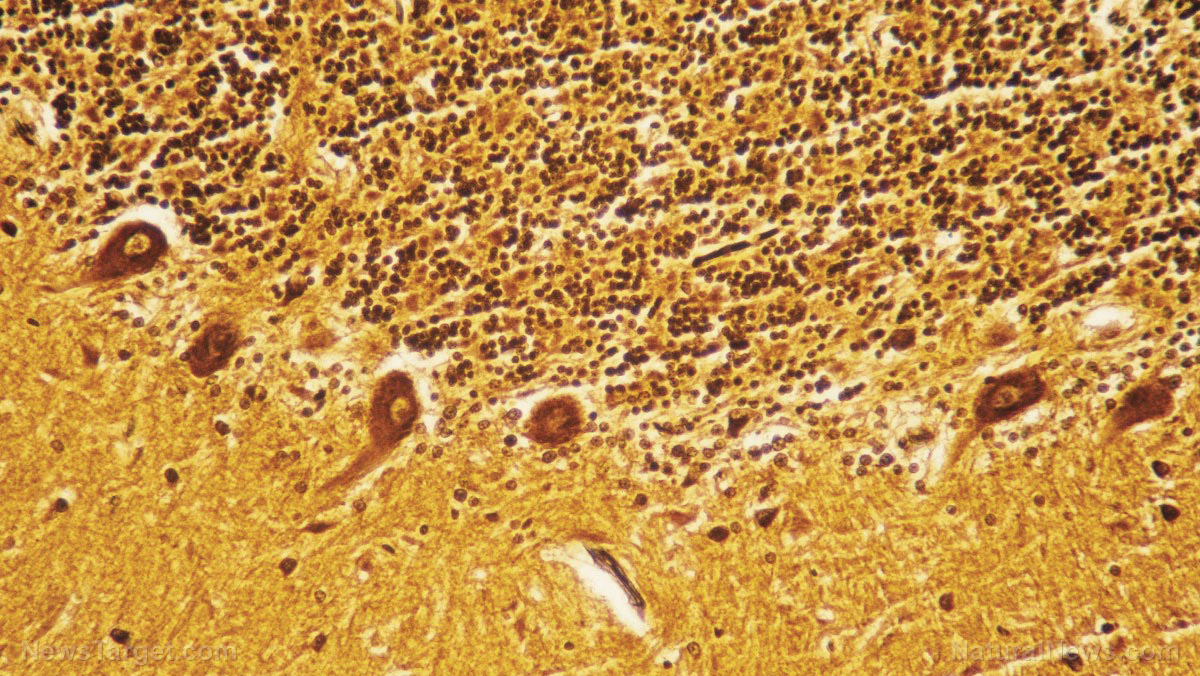

Traditional Chinese Medicine (TCM) helps patients with multiple sclerosis maintain their cognitive function

Rehmannia (Radix rehmanniae) is a staple of traditional Chinese medicine. This medicinal herb contains many beneficial compounds such as catalpol, which can protect against brain diseases. A recent study showed that the catalpol extract from Rehmannia could preserve the cognitive capabilities of people afflicted with multiple sclerosis. Multiple sclerosis inflames cerebral tissue, breaks down the […]